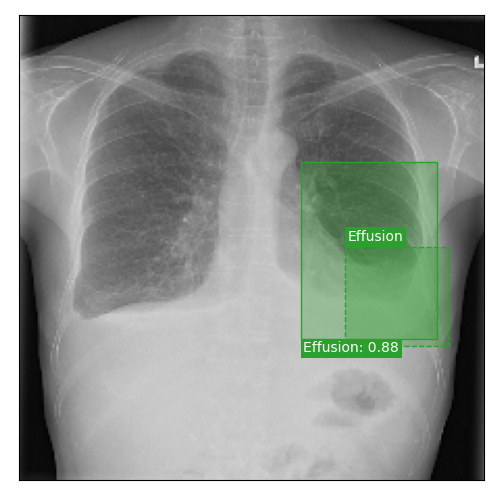

Qualitative Results

As shown in Fig. 4 Loc-ADPD detects cardiomegaly almost perfectly, as it is always exactly localized at one anatomical region. Other pathologies are detected but often with too large or too small boxes as they only cover parts of anatomical regions or stretch over several of them, which cannot be completely corrected using WBF. Detection also works well for predicting several overlapping pathologies. For qualitative comparisons between Loc-ADPD and MIL-ADPD, we refer to Appendix 0.B.